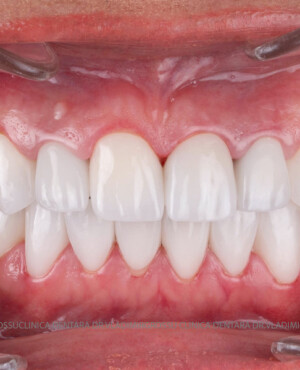

Transformările estetice și impactul reabilitării asupra vieții pacienților

Reabilitarea dentară produce o schimbare vizibilă și profundă în aspectul pacientului, cu efecte pozitive evidente asupra stimei de sine și a calității vieții. Mulți pacienți relatează bucuria redobândirii funcției masticatorii și dispariția complexelor legate de aspectul dentar.